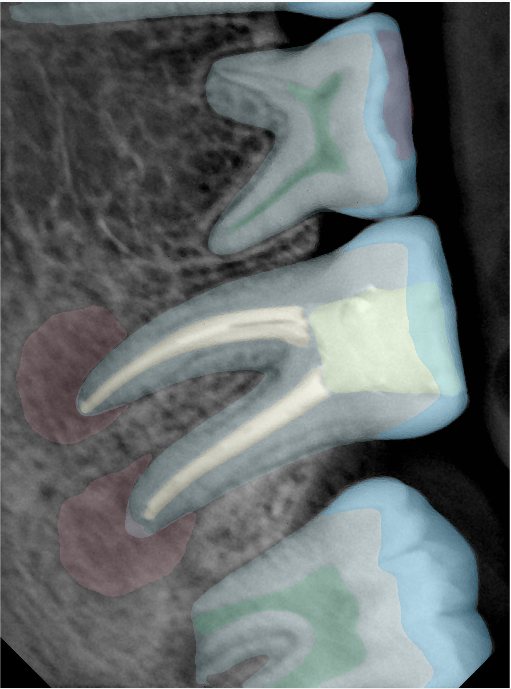

CR/DR 牙齿分割阶段记录

当前进展

- 完成了 CR/DR 牙齿相关分割训练

- 当前结果已经达到阶段预期,但仍有细节问题需要继续处理

相关测试

遇到的问题

- 训练过程中出现过 mask 下移问题

- 部分结果会出现 box 填充异常

- mask 边缘仍然有比较明显的锯齿感

参考

第二版算法问题测试